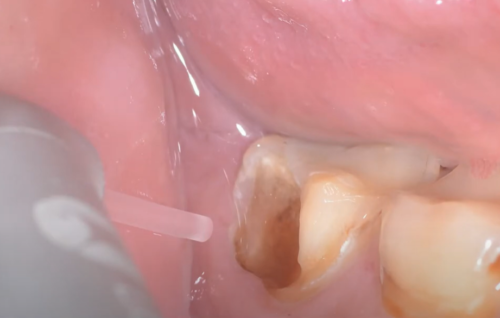

Hình ảnh: Làm sạch lỗ sâu với Laser LiteTouch Er: YAG